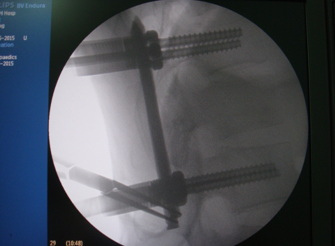

经皮椎弓根螺钉技术治疗胸腰椎骨折

采用C臂X线透视下椎弓根精确定位,做小切开,经皮钝性分离肌肉后,在X线监测下置入椎弓根钉,术中不需暴露椎旁肌肉、横突和关节突,显著减少出血,保护了肌肉以及脊神经后支,最大限度的避免手术导致的副损伤,再通过器械行骨折复位,或者在通道下完成微创椎管减压椎体间融合术。

我院骨科成功开展了多例腰椎骨折经皮椎弓根螺钉固定手术,该技术的开展填补了我院在这一领域的空白,这表明我院骨科专业技术水平发展处于全市领先水平。